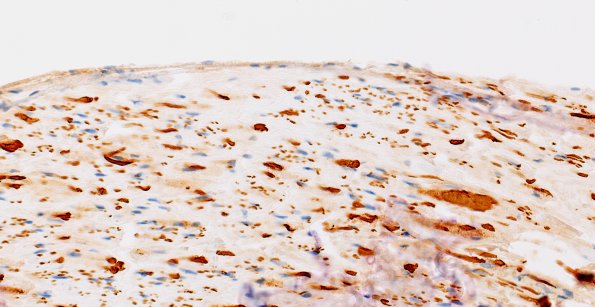

Washington University Experience | PERIPHERAL NEUROPATHY | 7A GUILLAIN-BARRE SYNDROME (GBS) | 4B2 (Case 4) NF 40X 2

In other sites there is degeneration of axons and axonal spheroids, as might be expected in axonal degeneration. (NF IHC)